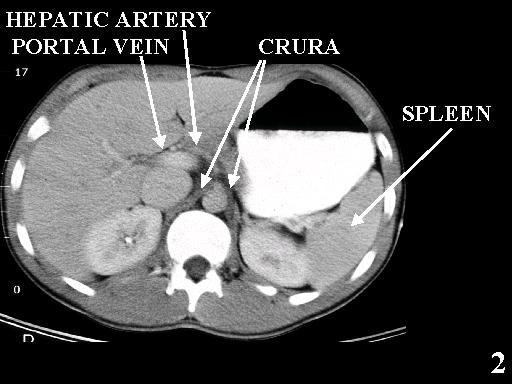

MS 190 CT 13